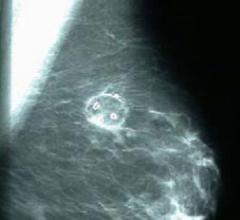

Despite decades of progress in breast imaging, one challenge continues to test even the most skilled radiologists ...